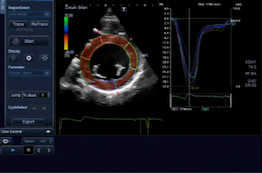

Echocardiography has emerged as the modality of choice for noninvasive evaluation of cardiac disease in the cancer patient. This tool is essential for the evaluation of left ventricular systolic and diastolic dysfunction, pericardial and valvular heart disease. However, echocardiograms are only routinely performed at the beginning of cancer therapy, in order to document a normal left ventricular systolic function. Further echocardiographic follow up during cancer therapy is performed only as a consequence of the onset of cardiac symptoms and/or signs, in particular following the administration of recognized cardiotoxic drugs or radiation therapy.

Rosa Sicari, FESC, from the CNR Institute of Clinical Physiology, Pisa, Italy and chairperson of the EAE Scientific Committee added, “The assessment of cardiac toxicity remains a critical issue in oncology. Ejection fraction, the time honored parameter of function, is not useful for the detection of early and subtle forms of cardiac dysfunction. New tools are needed and the evidence should be built in the near future with appropriately designed studies and with the common efforts of oncologists, cardiologists and pharmacologists. This document is not meant to fill the gap of knowledge but to provide the state of the art of ultrasound in this field and indicate new research pathways.”